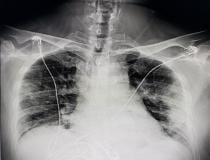

This photo gallery shows the variety of radiological presentations of COVID-19 (SARS-CoV-2) in medical imaging, including computed tomography (CT), radiograph X-rays, ultrasound, echocardiograms and magnetic resonance imaging (MRI). The radiology images show examples of typical COVID pneumonia in the lungs and the numerous complications the virus causes in the body in multiple organs, including the brain, kidneys, heart, abdomen and vascular system.

Ultrasound, especially hand-held ultrasound imaging devices, have become a primary imaging modality for novel coronavirus because of the ease to bag the device and sterilize it after use. CT and mobile X-ray systems are also used as front-line imaging systems for COVID-positive or suspected COVID patients.